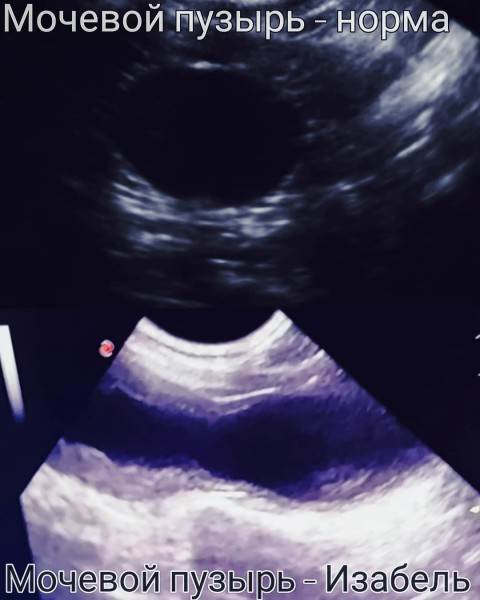

Мочевой пузырь кошки Изабель на УЗИ

На снимках, используемых в этой статье, кошка Изабель — являющаяся показательным примером того, что случится с органами мочевыделительной системы «спинальника», если животному не опорожнять мануально мочевой пузырь. Изабель утратила функцию произвольного мочеиспускания в возрасте котёнка, после чего целый год жила в приюте для бездомных животных, где не знали о необходимости мануально опорожнять мочевой пузырь кошке, которая не может осуществить диурез самостоятельно. За самостоятельное мочеиспускание воспринималось протекание по каплям на фоне переполнения.

Постоянное переполнение и перерастяжение мочевого пузыря превратили когда-то упругий «шарик» (мочевой пузырь) в растянутую атоничную «тряпочку». Качественно мануально опорожнять этот мочевой пузырь сейчас — очень тяжело даже опытным ветеринарным врачам.

В этом состоянии мочевой пузырь Изабель благоприятен для размножения в нём бактерий, так или иначе попадающих туда извне, диагноз — хроническая рецидивирующая осложнённая бактериальная инфекция, а единственный выход — ежедневный пожизненный приём антибиотика. Каждый день. Всю жизнь. Антибиотик. Иначе — тухлая красная моча.